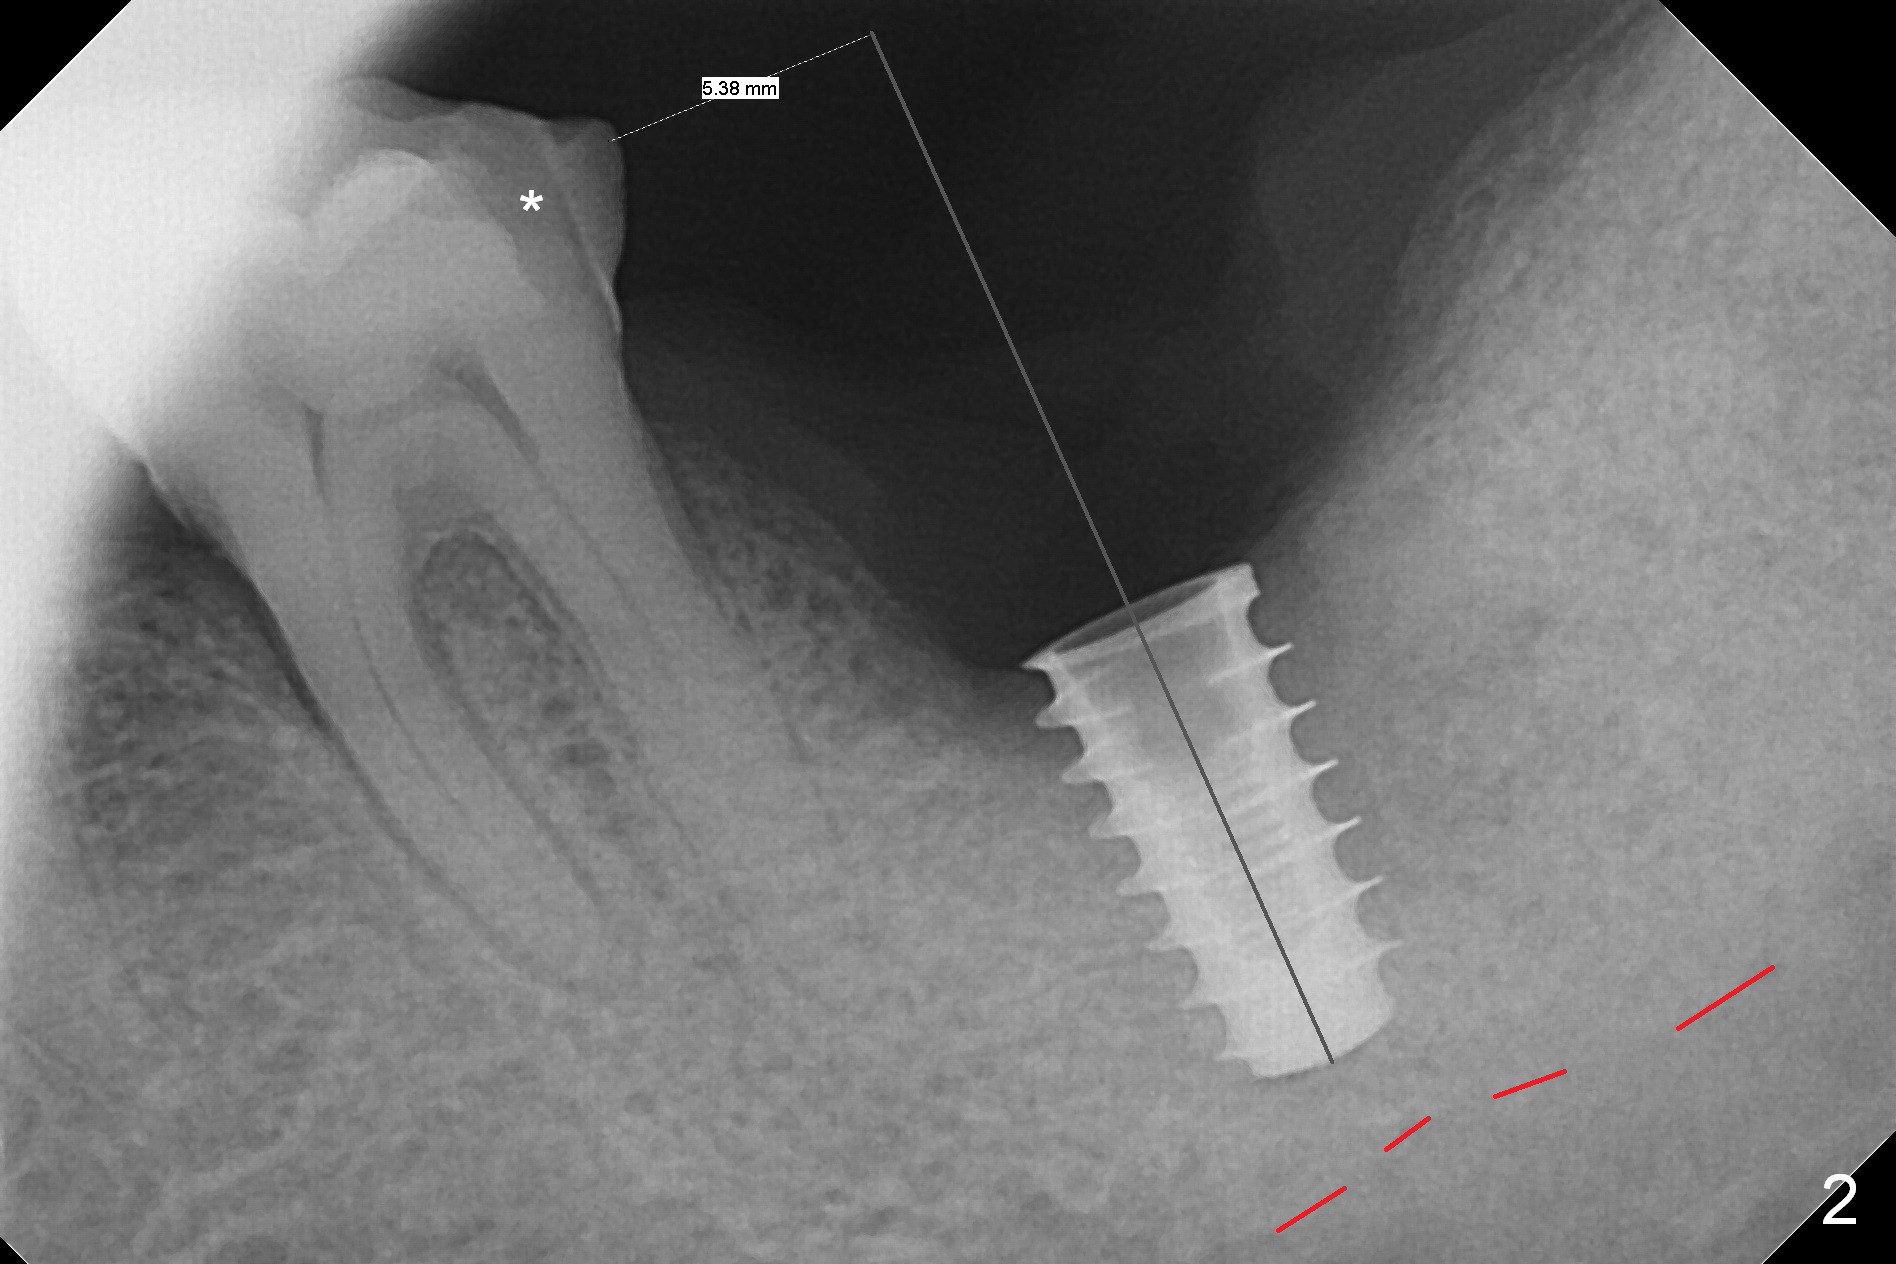

When the tooth #18 is extracted, the buccal and lingual plate are absent. Initial osteotomy is established in the middle of the socket (Fig.1). After 4.3 mm Magic Drill (15 mm from the buccal gingival margin, new bone ~ 4 mm), a 5x9 mm IBS dummy implant is placed with correct trajectory (Fig.2). Since the bone density is seemingly high, the same size of a definitive implant is placed with primary stability. The trajectory is found not ideal after bone graft and insertion of an abutment (data not shown). The stability is lost when the trajectory is changed. No primary stability is achieved with a larger (5.5x9 mm) implant. Tatum tapered taps (6x17, 7x17 and 8x17 mm) are used. The latter obtains stability with contact with the mesial and distal crests (Fig.3 *). A 8x14 mm tissue-level implant is placed with insertion torque ~ 55 Ncm (Fig.4). A 6x3 mm abutment (Fig.4 A) is placed to retain an immediate provisional (Fig.5 P). The drawback of the extra large implant is lack of bone buccolingually. Oral hygiene is emphasized so that the buccal and lingual bone have chance to regenerate. Fortunately there appears to be no paresthesia postop.